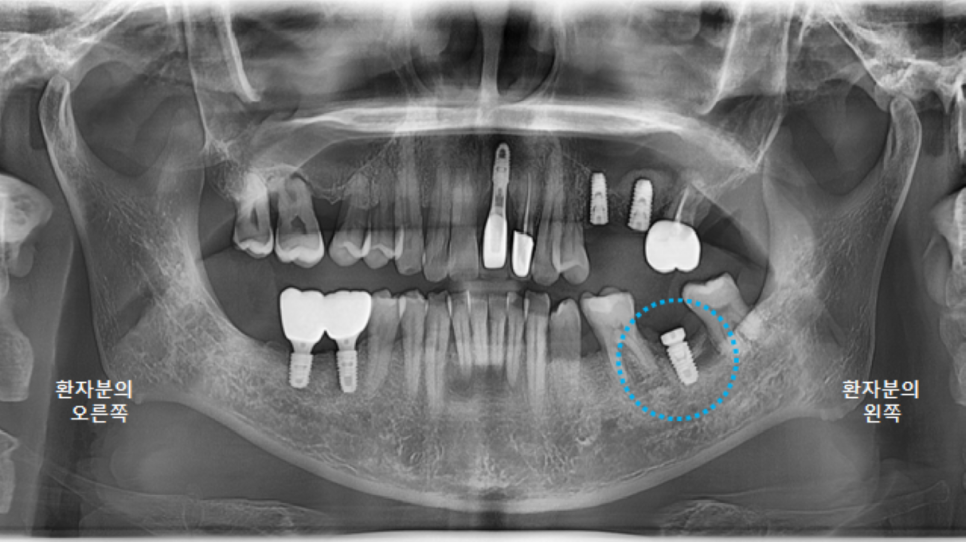

이제 다시 왼쪽으로 돌아옵니다.

왼쪽아래 큰어금니의 남아있던 뿌리를 제거한지 4개월이 지났습니다.

염증이 너무 심한 상태여서 치유가 빠르지는 않습니다.

뼈가 더 잘 찰 수 있도록, 뼈이식을 진행합니다.

다시 충분히 치유를 기다려봅니다.

5~6개월 정도 예상합니다.

그리고 다시 파노라마 엑스레이를 촬영했습니다.

최상의 컨디션은 아니지만,

어느정도 치유가 되었기에 3차원 CT 촬영 후, 왼쪽아래 큰어금니 임플란트 수술을 진행하도록 합니다.